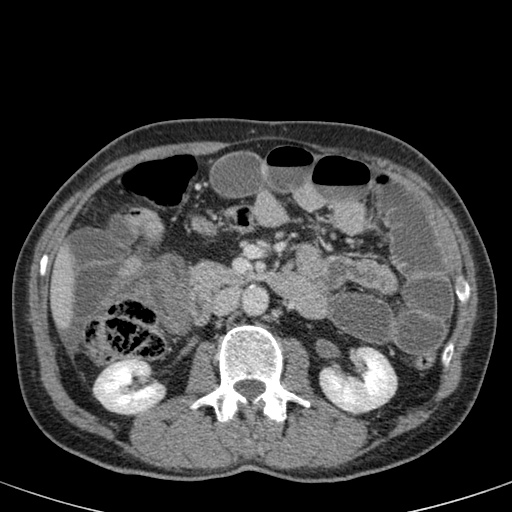

Tắc ruột dạng quai kín với các quai ruột giãn xếp theo hình nan hoa. Có dày thành ruột và phù nề mạc treo gợi ý thiếu máu cục bộ

Một hình ảnh quan trọng khác của tắc ruột dạng quai kín là các quai ruột non giãn xếp theo hình nan hoa với các mạch máu mạc treo hội tụ về một điểm trung tâm.

Hình ảnh này hầu như luôn do xoắn ruột non gây ra.

Các dấu hiệu thiếu máu cục bộ trong tắc ruột dạng quai kín tương tự như ở bệnh nhân thiếu máu mạc treo do các nguyên nhân khác:

- dày thành ruột

- phù nề mạc treo

- cổ trướng

- sự ngấm thuốc của thành ruột trong thiếu máu cục bộ có thể bình thường, tăng hoặc giảm.